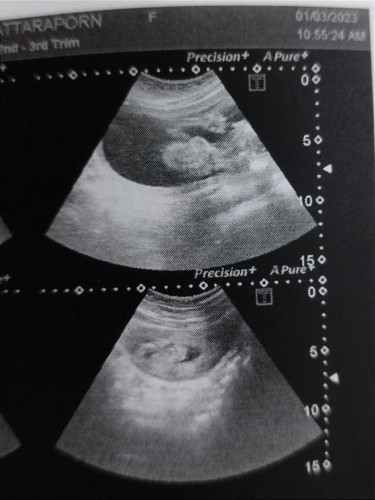

อัลตร้าซาวด์เพศ

วันนี้แม่ได้ไปซาวด์ดูเพศน้องมาค่ะก่อนไปเราก็ลูบท้องพูดบอกลูกทุกวันค่ะให้อ้าขาโชว์วันนี้ได้เห็นจังๆๆไปเลยจ้า คุณแม่ท่านอื่นละค่ะเป็นไงกันบ้าง 19w4d #ทีมลูกชายกรกฎาคม

13 กรกฎาค่ะ ยอมเสี่ยงซาวด์ 2มิติดูตอน 20wค่ะดูลูบท้องบอกให้น้องให้ความร่วมมือหน่อย อย่าให้แม่เสียเงินฟรี สุดท้าย ก็ได้เห็นค่ะ ป้าหมอบอกผชแต่แม่แอบลุ้นผญค่ะ รอสัก7เดือนแม่ว่าจะไปซาวด์ 4มิติอีกรอบค่ะ😄😄ตอนนี้ 21w

ไปซาวมาตอน19วีค4วันเหมือนกันค่ะ อ้าโชว์เลย สงสัยนั่งรถนาน555 ดิ้นเก่งด้วยหมอบอก555 น้องผู้ชายเหมือนกันค่ะ

17วีค 5วัน ก่อนซาวน์เราก้อพูดกับลูกว่าหนูเพศอะไรโชว์มาเลยลูก ได้ผลค่ะ น้องเป็นผู้ชายค่ะ ทีมกรกฎาคมค่ะ

ซาวน์ตอน 17w6d ลูบท้องบอกลูกเหมือนกันเลยค่ะให้อ้าโชว์ป้าหมอไปเลยเพศไหนเเม่ก็รักหมดค่ะ ได้ผลจริงๆ #ลูกสาว 😍

บ้านนี้พึ่งไปซาวมา 17+4wทีแรกหนีบใว้พอป้าหมอบอกว่าขอดูหน่อยอ้าขาโชว์เลยจ้า ได้สาวน้อยมา1ชีวิต 🥰

19w1วัน โชว์จู๋ให้หมอดูเลยค่ะ ได้ผช อิแม่ยิ้มแก้มปริเลย นั่งรอหมอซาวด์ ดิ้นรอเลยค่ะ555

19w วันนี้พอดีค่ะคุณหมอนัดวันนี้บอกได้ลูกชายถูกใจอีแม่สุดๆค้า